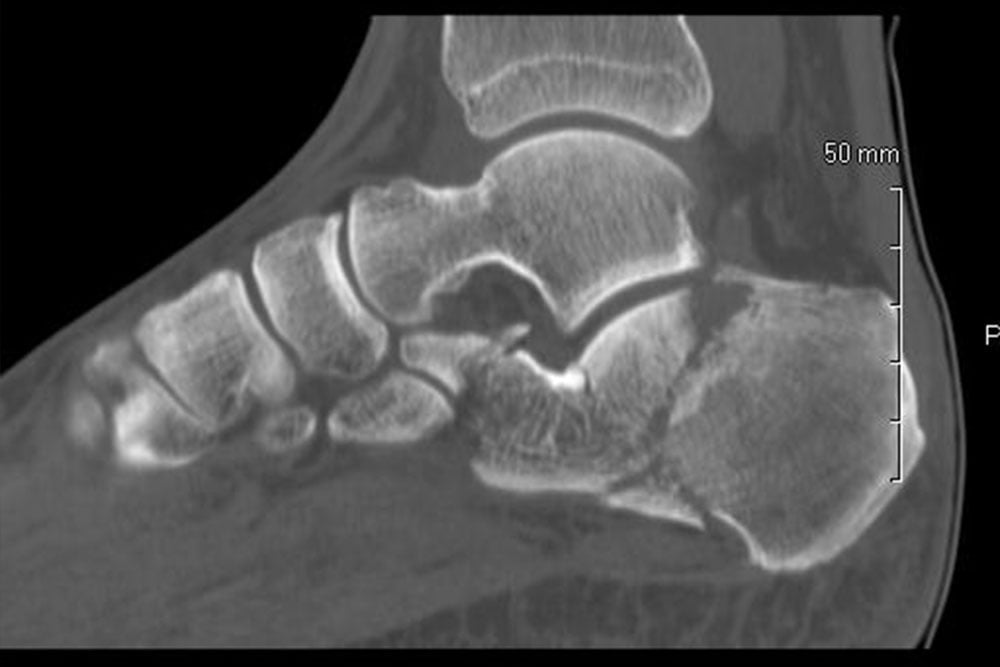

We also work closely with local outpatient laboratories and radiology offices to obtain quick results for any necessary diagnostic tests or imaging.

The foot is one of the most complex structures of the human body. Each fully matured foot is composed of 28 bones, more than 30 joints and hundreds of soft tissue structures including ligaments, tendons, muscles, nerves and blood vessels. There are various orthopedic, rheumatic, neurologic, dermatologic and vascular pathologies that can affect a person’s foot, and a podiatric foot and ankle specialist is skilled to address many of these disorders.